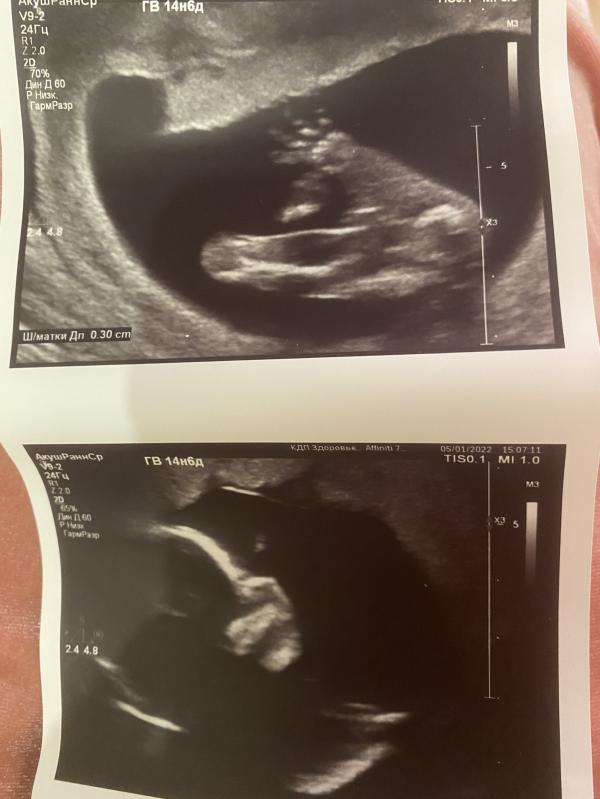

Были вчера с мужем на внеплановом узи, насмотрелись на малышка😍😍😍точнее малышку, будет у нас вторая дочка🥰 на долю секунды словила мысль расстройства, когда дочь сказала что в животике братик и ждёт она исключительно брата и не нужна ей никакая сестра😁 надеюсь отпустит ее это😂 тяжело будет с именем, у старшей оно необычное, но при этом очень красивое, как будем подбирать не менее потрясающее даже и не знаю🙈 муж как и с первой, сказал Игорем назовём 😂